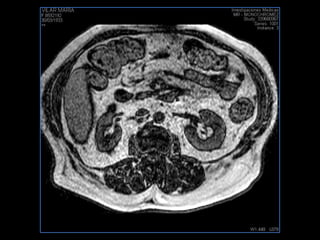

PROTOCOLO abdomen COR T2, AXIAL supresion grasa AX T1 +SAG T2  CON   GADOLINIO :  COR T1+AX T1(DIN) SAT: NO  FASE: RL THK: 6MM  COIL:  GAP: (FACTOR 1.4) 2MM FOV: 40 CM NEX:2 SINCRONIZACION RESPIRATORIA EN 3 O 4 CICLOS ALE

PROTOCOLO pancreas/ riñon AXIAL fat sat /AX in phase out phase AX T1 +SAG T2  COR T2, CON   GADOLINIO :  COR T1+AX T1(DIN) SAT: NO  FASE: RL THK: 4MM  COIL:  GAP: (FACTOR 1.4) 1MM FOV: 40 CM NEX:2 SINCRONIZACION RESPIRATORIA EN 3 O 4 CICLOS ALE